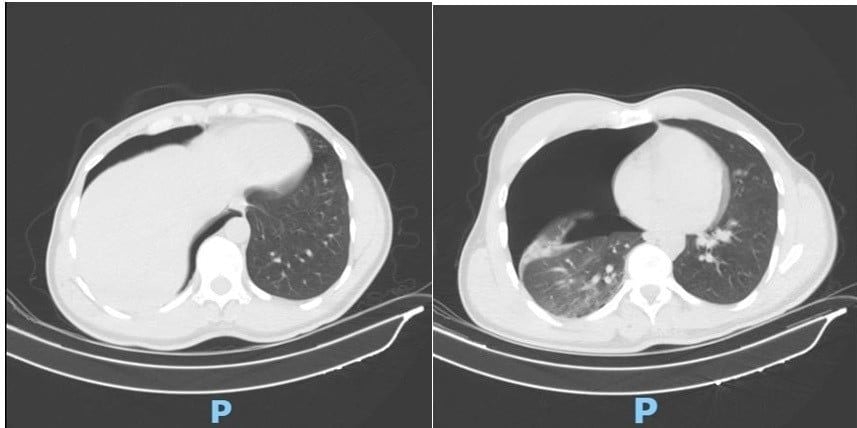

Emergency CT scans of the chest and blood vessels identified a large right-sided pneumothorax compressing the lung, fractures of the second to fourth ribs on the right side, and a severely displaced fracture of the middle third of the right clavicle.

As the patient’s respiratory condition worsened, a surgical team from the Cardiothoracic and Vascular Surgery Department carried out an emergency right pleural drainage procedure in the early hours of the same day. The intervention allowed the lung to re-expand, and the patient’s breathing improved markedly within hours.